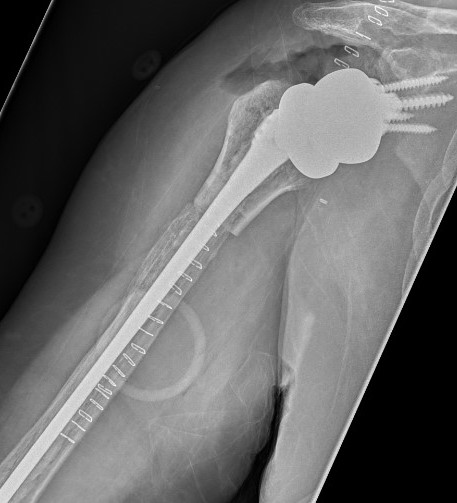

Hum shafthum shaftHum shaft

Stable humeral component treated with ORIF

hum #Hum #Hum #

Unstable humeral component